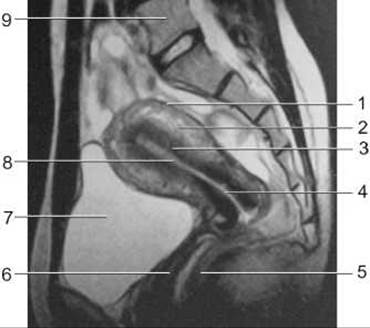

Мал. 258. Магнітно-резонансна томограма органів жіночого таза у сагітальній площині.

1 - периметрій;

2 - міометрій;

3 - ендометрій;

4 - канал шийки матки;

5 - пряма кишка;

6 - Піхва;

7 - сечовий міхур;

8 - порожнина матки;

9 - V поперековий хребець.

Магнітно-резонансний метод дослідження жіночих статевих органів виконується без підготовки у положенні хворої на спині при поверхневому диханні. На Т1-зважених зображеннях матка має гомогенну структуру, чіткі контури і дає сигнал середньої інтенсивності. На Т2-зважених зображеннях можна визначити будову матки: ендометрій дає сигнал високої інтенсивності, міометрій - сигнал середньої інтенсивності у товстій зовнішній зоні і сигнал низької інтенсивності у вузькій внутрішній зоні; шийка матки також дає низькоінтенсивний сигнал, що пов’язано з переважанням у ній, як і у внутрішній зоні міометрію, сполучної Тканини; шийковий канал, заповнений слизом, дає сильний сигнал (мал. 258). Яєчники на МРТ визначаються частіше, ніж на КТ. На Т1-зважених зображеннях вони дають слабкий сигнал. На Т2-зважених зображеннях строма яєчників дає слабкий сигнал, а фолікули - сильний сигнал.